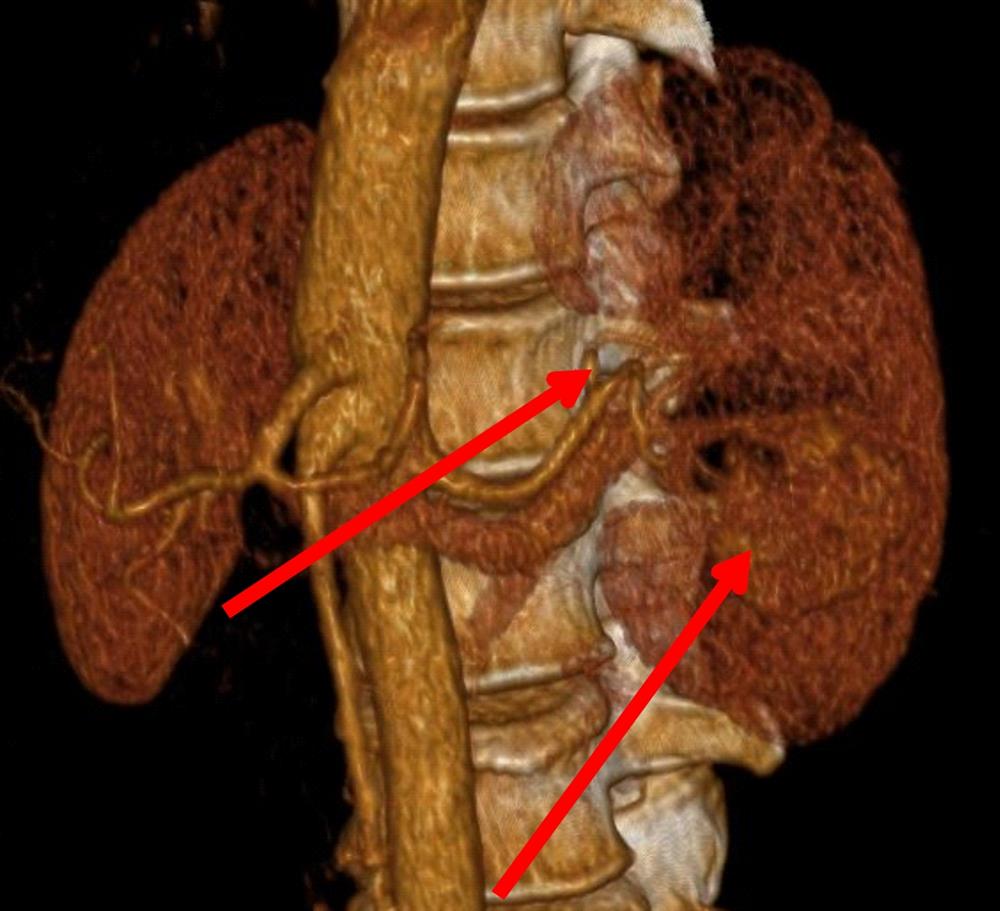

Компьютерная томография

Это одно из самых нужных исследований для обнаружения и изображения опухоли почки. КТ может представить точную информацию о размере, границах и месте расположения опухоли в почке. Также это исследование полезно для проверки наличия распространения опухоли в ближайшие лимфоузлы или органы и ткани вне почки. Если необходима биопсия (взятие небольшого кусочка опухоли), КТ можно использовать для выбора траектории проведения биопсийной иглы в опухоль.

Это одно из самых нужных исследований для обнаружения и изображения опухоли почки. КТ может представить точную информацию о размере, границах и месте расположения опухоли в почке. Также это исследование полезно для проверки наличия распространения опухоли в ближайшие лимфоузлы или органы и ткани вне почки. Если необходима биопсия (взятие небольшого кусочка опухоли), КТ можно использовать для выбора траектории проведения биопсийной иглы в опухоль.

Магнитно-резонансная томография

МРТ реже используется у пациентов с подозрением или установленным диагнозом опухоли почки, чем КТ. Наиболее часто этот метод может применяться при подозрении на распространение опухоли в просвет крупных сосудов, таких как почечная вена и нижняя полая вена, так как МРТ дает изображения кровеносных сосудов более высокого качества, чем КТ. Также МРТ может применятся при подозрении на распространение опухоли в головной или спинной мозг.